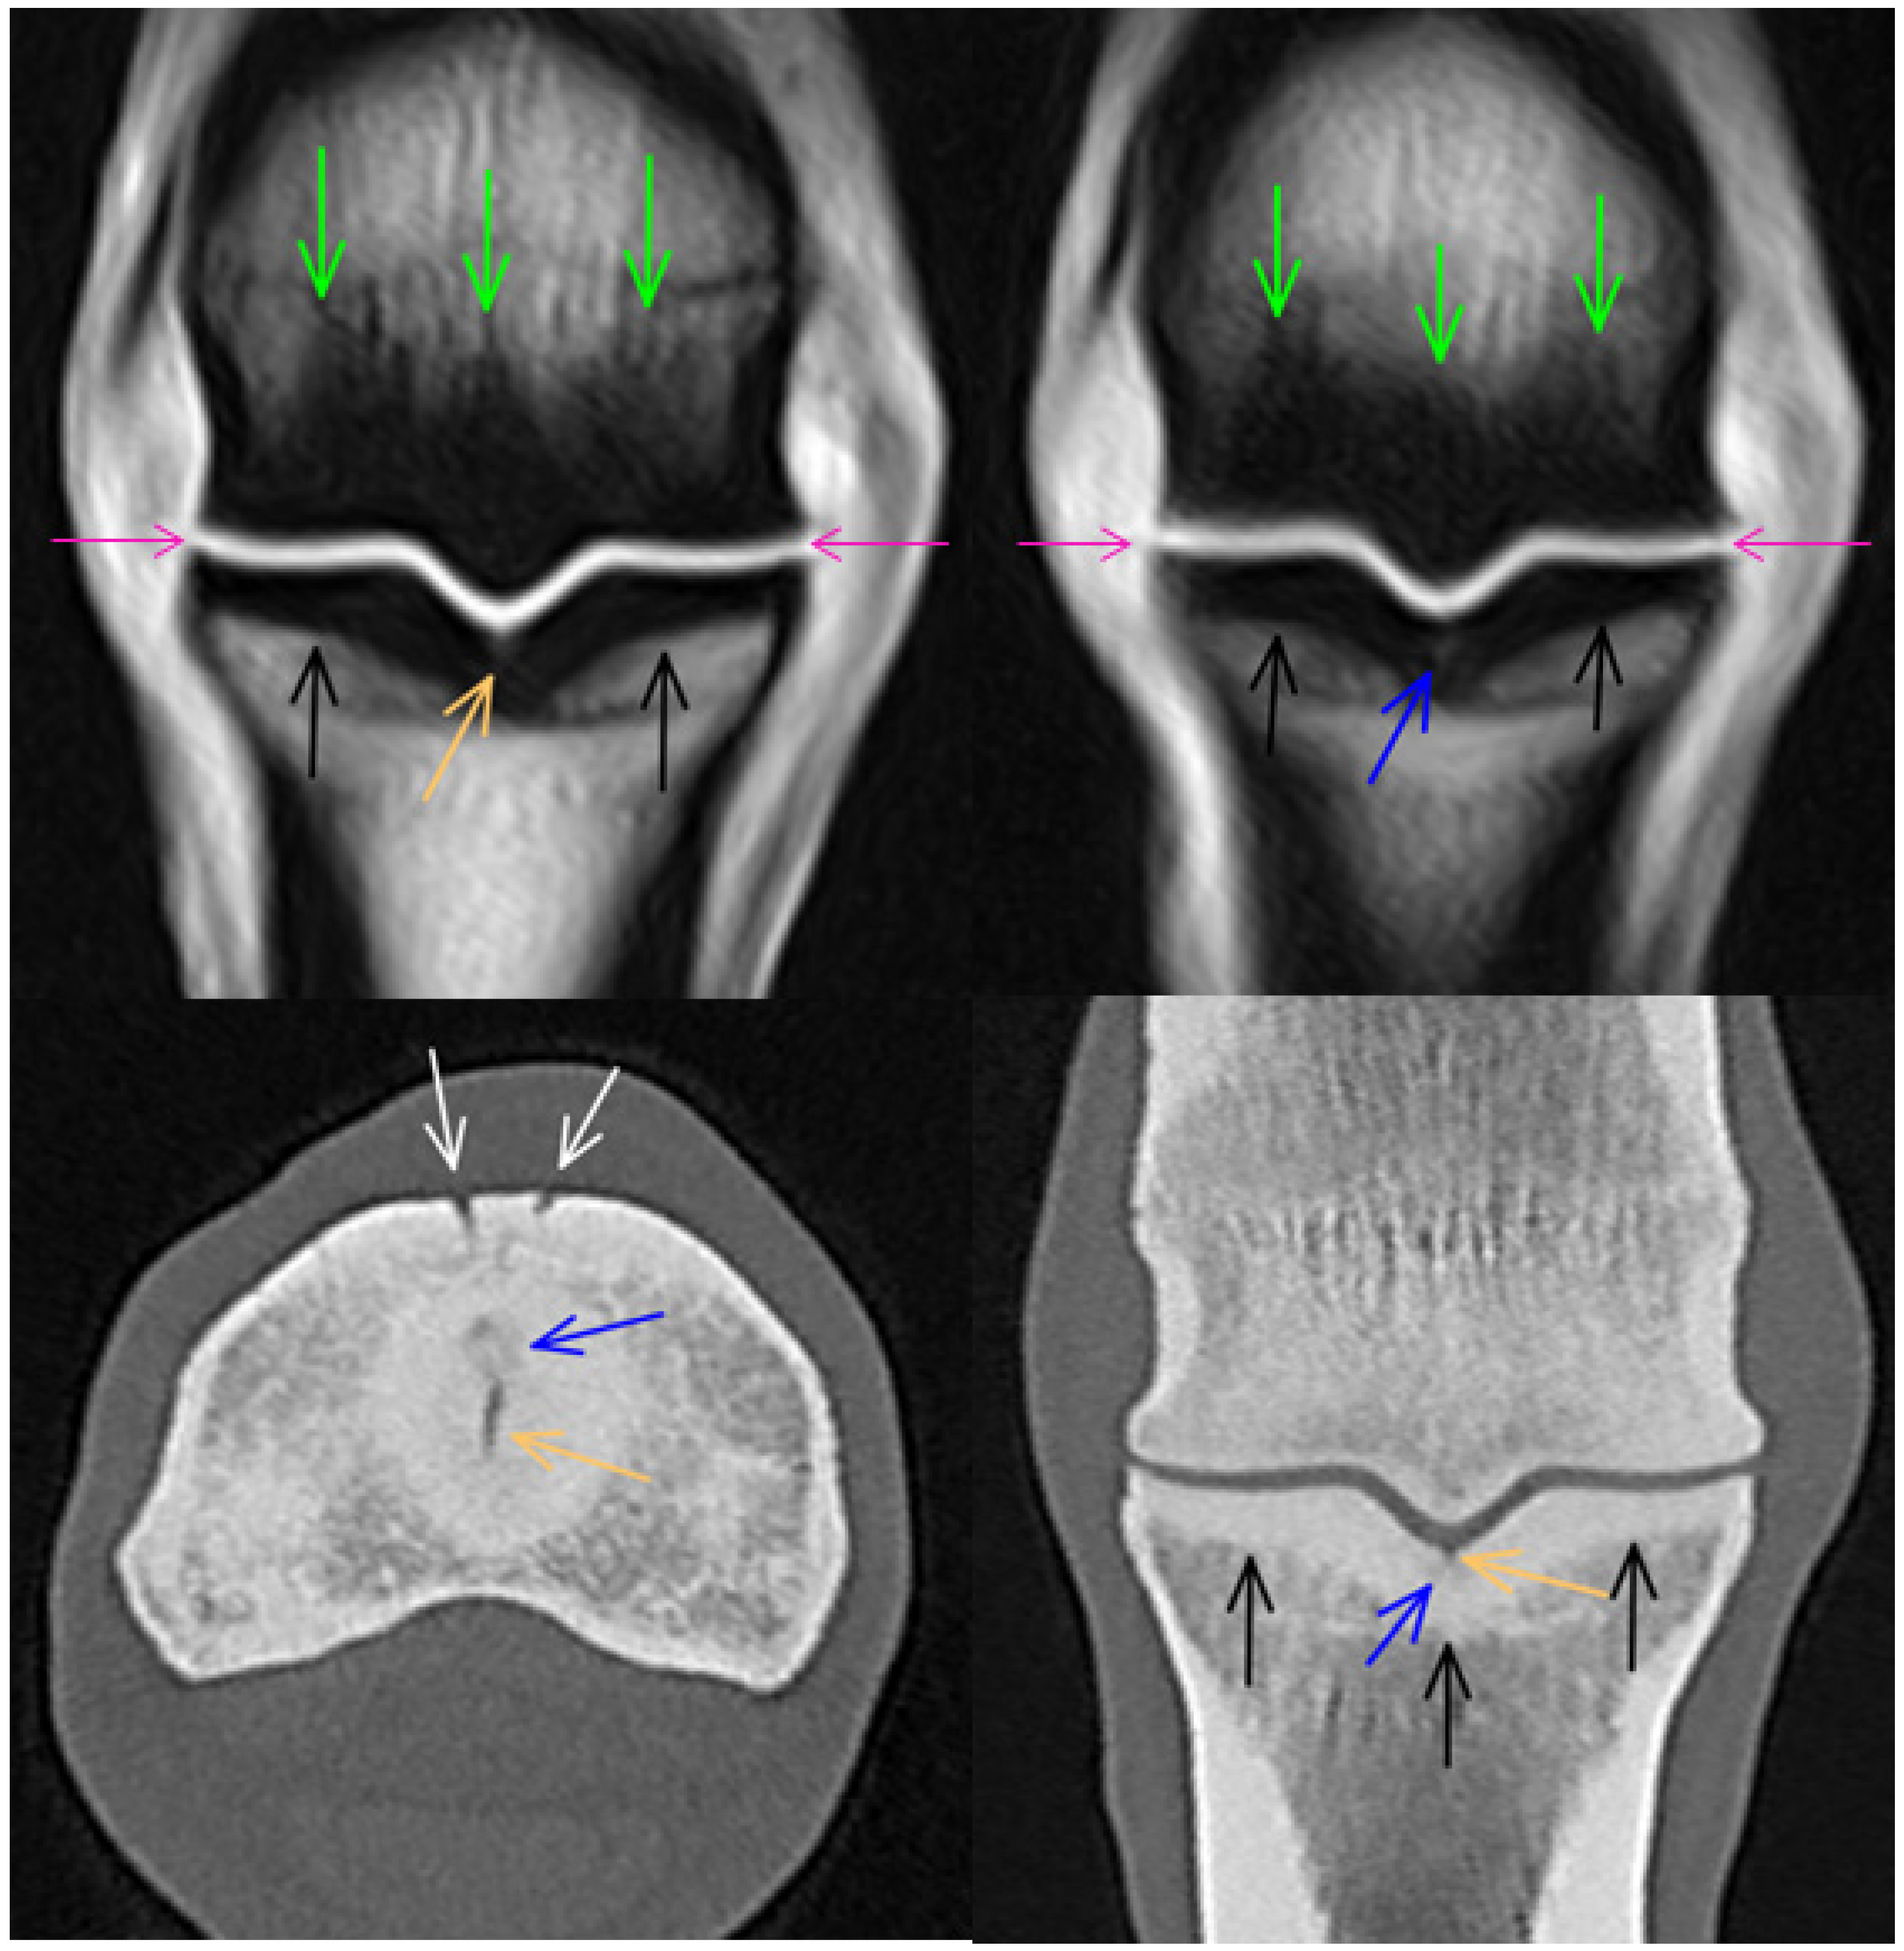

3.1. Third Metacarpal Bone

3.2. Proximal Phalanx

3.3. Proximal Sesamoid Bones